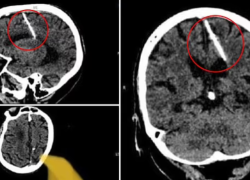

Por medio de una tomografía computarizada, una mujer rusa de 80 años descubrió que ha tenido una aguja de tres centímetros enterrada en su cerebro desde que era bebé.